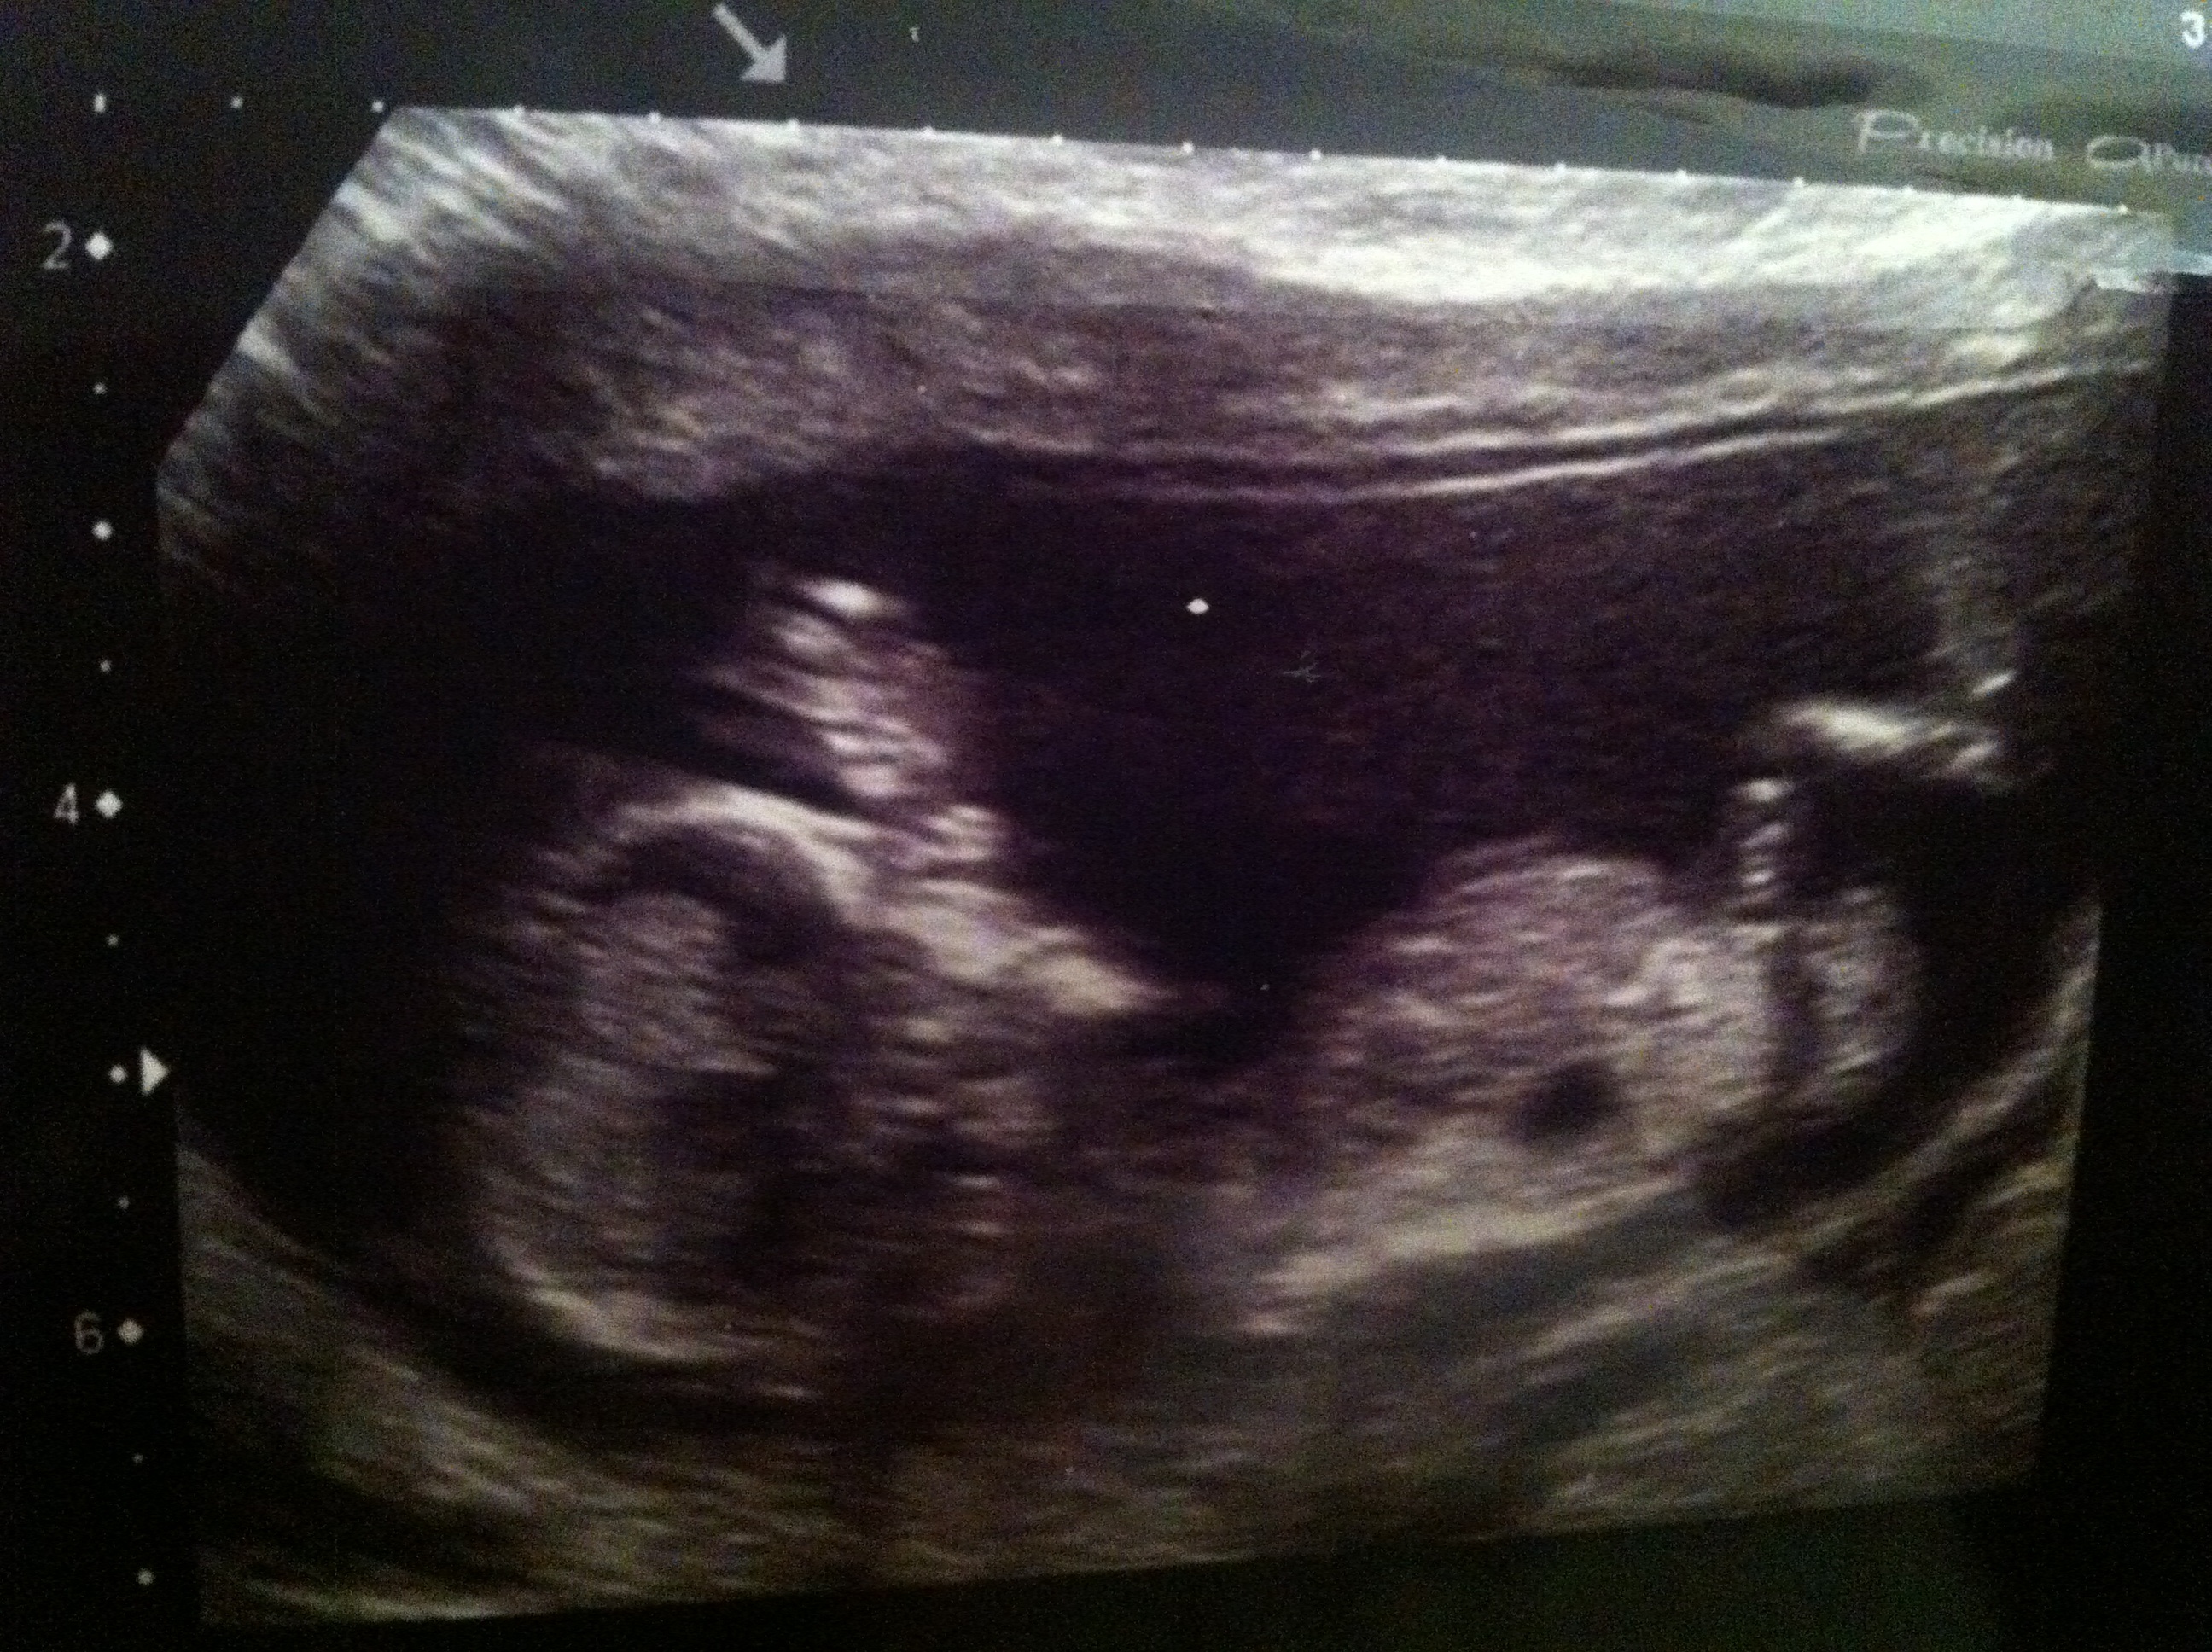

No idea if theres a visible nub or not sorry but hope so! Curious as to what people think the gender of my baby is! :) thanks xAttachment 9760

Think I might be able to see nub in first pic, if so, I'd guess boy.

Maybe a hint of a girl nub??